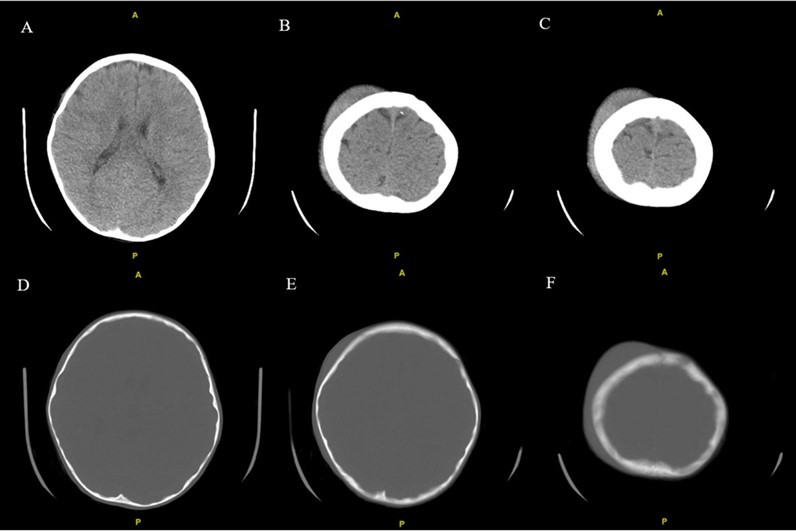

From a musculoskeletal standpoint, MRIs of the cervical, thoracic, and lumbar spine were within normal limits. The patient was started on scheduled acetaminophen for pain management. A CT of the head without contrast showed right high convexity scalp soft tissue swelling without acute intracranial abnormality (Figure 1A – 1F). A complete bone survey was negative for sources of trauma (Figure 2B – 2I) but did note calvarial soft tissue edema (Figure 2A). A head ultrasound confirmed the fluctuance on the patient’s skull to be a subgaleal hemorrhage (Figure 3A – 3C) of 9 mm thickness at its greatest.

Figure 1A - 1F.Noncontrast CT examination of the brain. Multiple axial images were obtained. Images listed from superior to inferior. Adjustment of the MA and/or KV was done according to the patient's size. Findings include right high convexity scalp soft tissue swelling without acute intracranial abnormality.